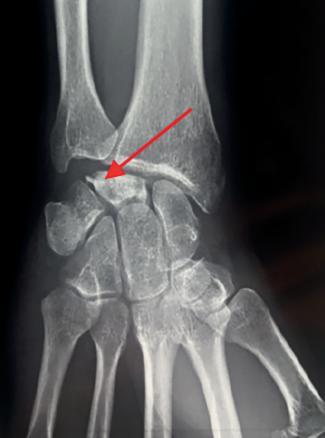

La radiographie montre une fragmentation partielle de cet os avec compactage osseux (fig. 1).

La maladie de Kienböck est une affection rare correspondant à une nécrose (dévitalisation) d’un des 8 os du carpe : le lunatum (fig. 2). On parle aussi de nécrose aseptique du semi-lunaire ou encore lunatomalacie. Cette pathologie atteint plus souvent les hommes (7/1) âgés de 20 à 40 ans.

La radio standard en première intention confirme le diagnostic. Elle met en évidence diverses modifications du lunatum au fur et à mesure de l’évolution (sur plusieurs années ; tableau) et les anomalies morphologiques citées ci-dessus. L’IRM est indiquée en seconde intention, en cas de normalité de la radio (stade précoce) ou pour préciser les lésions (bilan préopératoire).